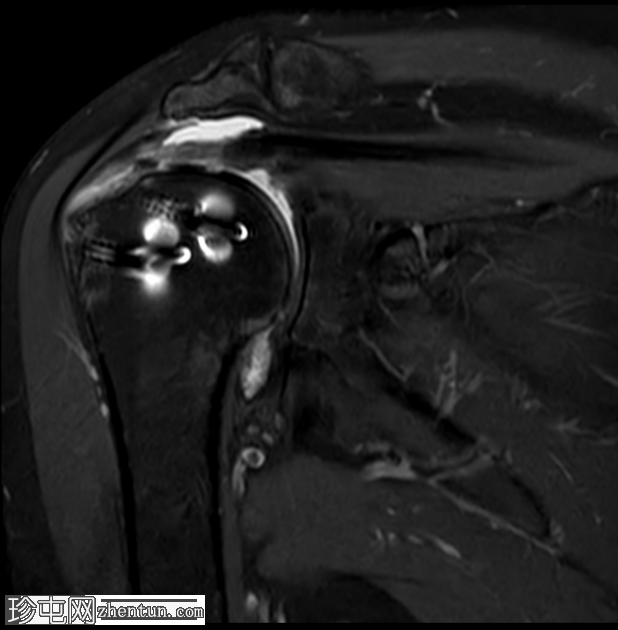

轴位T2加权像

脂肪抑制像

T2加权像显示近端锚钉周围有液体信号,提示锚钉松动,这并非正常的术后表现,提示骨整合不牢固。

MRI 诊断锚钉松动的依据是,在骨内锚钉周围可见晕圈状液体信号。